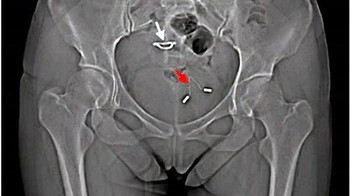

Doktor pakar telah menjalani pemeriksaan X-ray padanya dan menjumpai sesuatu yang mengejutkan.

X-ray menunjukkan peranti IUD yang beliau tanam telah menembusi rahim dan kini berada di pundi kencing!